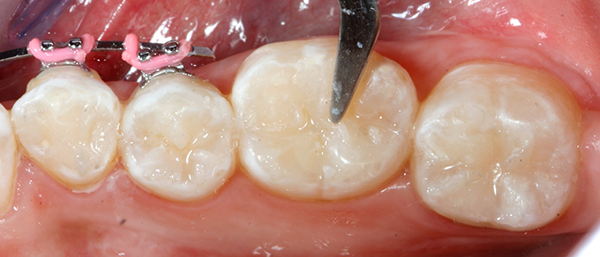

The following treatment sequence depicts one quadrant of her restorations. The teeth addressed were teeth #18-21.

After local anesthetic was administered, all visible decay was removed (Fig. 1) and, following the latest Dental Caries 2018: New Insights recommendation, all “affected” dentin layers were also removed. The preparation was disinfected with 5 percent gluteraldehyde-35 percent hydroxylethyl methacrylate (HEMA) formulations applied with Ball-Point Applicators™by KaVo Kerr.

Fig. 1 Fig. 2

After the two separate one-minute applications of disinfectant, the restorations were suctioned to achieve a damp surface.2 This step was followed by the application of OptiBond™ All-In-One self-etching dental adhesive by KaVo Kerr with Ball-Point Applicators (Fig 2 ).